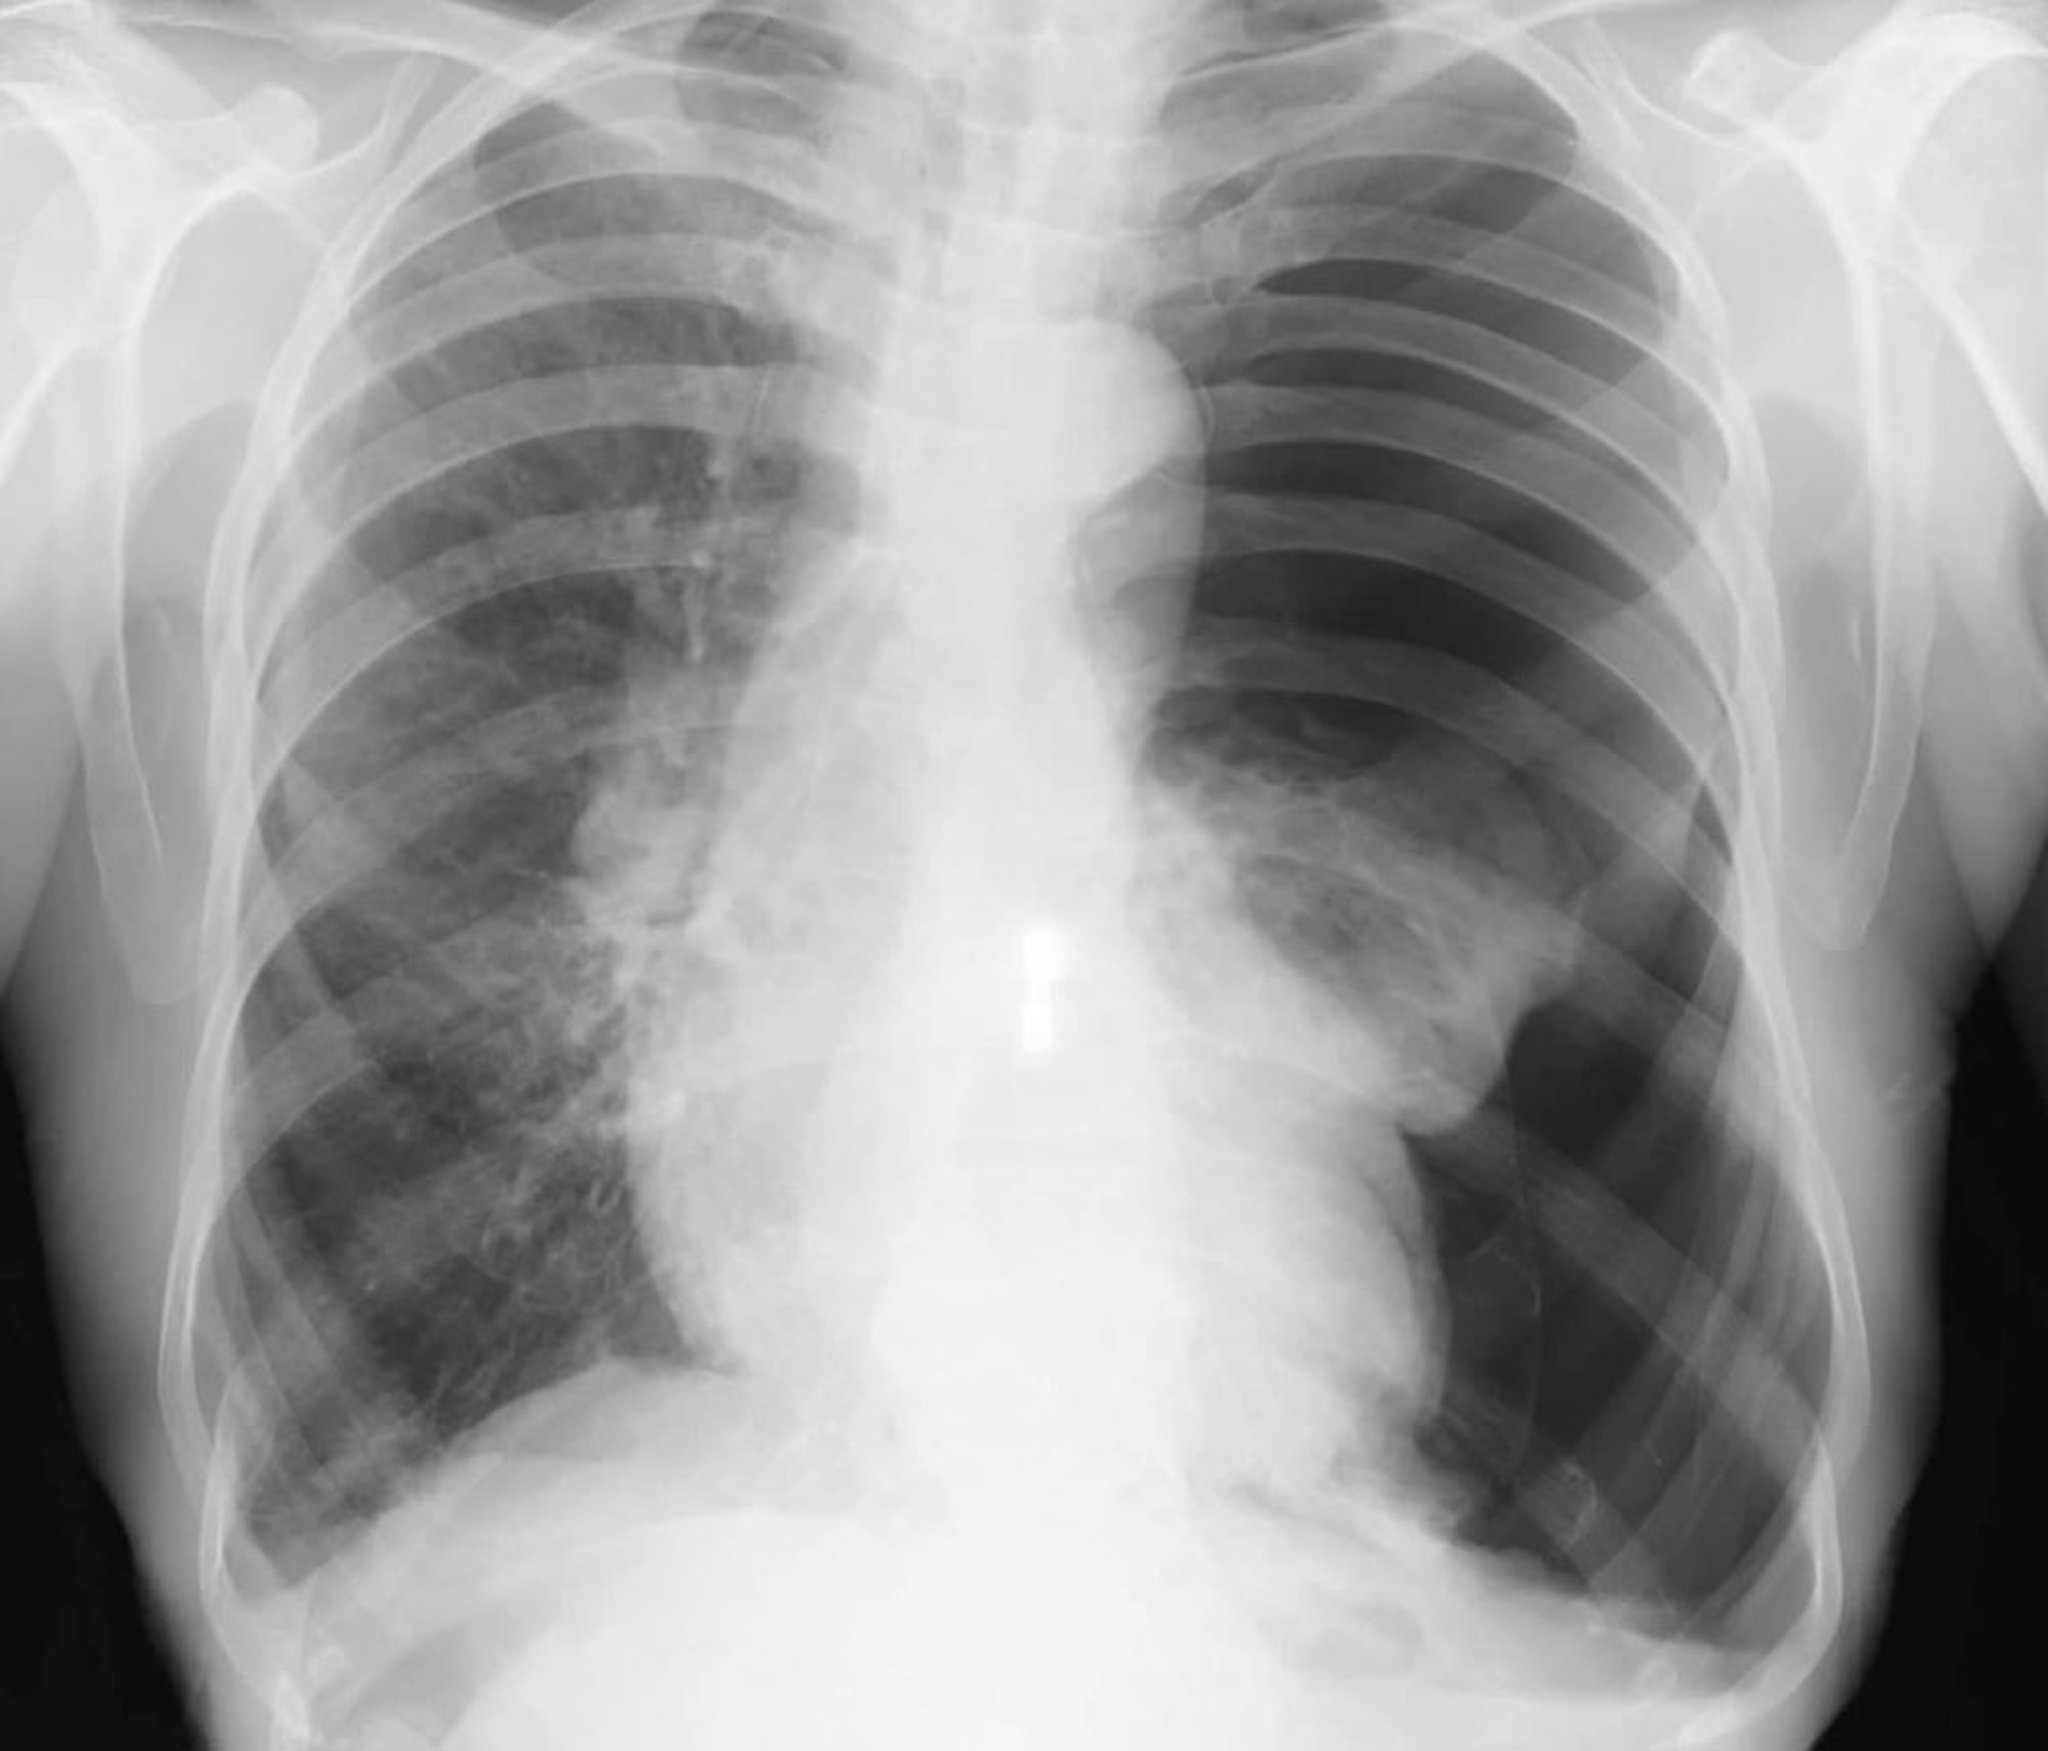

El diagnóstico se sospecha en pacientes cuya condición es estable pero que tienen disnea o dolor torácico pleurítico y por lo general se confirma con una radiografía de tórax inspiratoria en posición de pie. La densidad del tejido pulmonar aumenta si se obtienen placas en espiración, lo que aumenta la diferencia de contraste entre el aire en el espacio pleural y el tejido pulmonar adyacente (que tiene menos aire debido a una combinación del estado espiratorio y algun colapso). El aire radiotransparente y la ausencia de marcas pulmonares yuxtapuestas entre un lóbulo o pulmón contraído y la pleura parietal son diagnósticos de neumotórax. En los neumotórax grandes, se observan la desviación traqueal y el desplazamiento mediastínico. El diagnóstico también puede establecerse mediante ecografía realizada a la cabecera del paciente si la enfermedad pulmonar subyacente no impide la visualización adecuada.

El tamaño de un neumotórax se define como el porcentaje del hemitórax que está vacío. Este porcentaje se calcula mediante la resta de 1 menos la relación de los cubos del ancho del pulmón y del hemitórax. Por ejemplo, si el ancho del hemitórax es de 10 cm y el ancho del pulmón es de 5 cm, la relación es 53/103= 0,125. Por lo tanto, el tamaño del neumotórax es de alrededor de 1 menos 0,125 u 87,5%. Si hay adherencias entre el pulmón y la pared torácica, el pulmón no se contrae en forma simétrica, el neumotórax puede aparecer como atípicos o tabicado y el cálculo no es exacto.

Los neumotórax pequeños (p. ej., < 10%) a veces se pasan por alto en la radiografía de tórax. En los pacientes con posible neumotórax, los reparos pulmonares deben ser rastreados hasta el borde de la pleura en la radiografía de tórax. Incluso los neumotórax grandes pueden no ser evidentes en radiografías en decúbito supino, y debe buscarse específicamente el signo del surco profundo (un ángulo costofrénico anormalmente profundo), ya que puede ser el único signo de neumotórax en la radiografía de un paciente en esta posición. Las situaciones que imitan un neumotórax en la radiografía son ampollas enfisematosas, pliegues cutáneos, sábanas plegadas de la cama del paciente y superposición de las marcas del estómago o del intestino sobre los campos pulmonares.